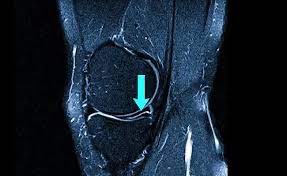

Классификация: разрыв мениска Stoller по МРТ

Для точной оценки повреждений на МРТ используется система Stoller — она делит изменения мениска на четыре степени:

🔹 Stoller III — подтверждённый разрыв мениска

Stoller IIIA и Stoller IIIB: в чём разница?

Критерий | Stoller 3A | Stoller 3B |

|---|---|---|

🧭 Локализация сигнала | Повреждение в продольной проекции (сагиттальный срез) | Повреждение во фронтальной проекции (корональный срез) |

🔬 Тип разрыва | Продольный вертикальный разрыв | Радиальный или горизонтальный разрыв |

📍 Расположение | Чаще ближе к телу мениска | Чаще ближе к основанию |

🔄 Влияние на стабильность | Может быть стабильным | Чаще нестабилен, может вызывать «зажёвывание» |

⚠️ Прогноз | Нередко требуется артроскопия (шов/менискэктомия) | Часто требуется артроскопия (шов/менискэктомия) |

Разрыв мениска Stoller 3A — вертикальный разрыв, виден на сагиттальном срезе МРТ.

Разрыв мениска Stoller 3B — горизонтальный или радиальный, лучше виден на фронтальном (корональном) срезе.

И 3A, и 3B означают, что линия разрыва достигает поверхности мениска, поэтому в большинстве случаев нужно хирургическое лечение.

МРТ коленного сустава — определяет степень разрыва мениска Stoller и тип повреждения